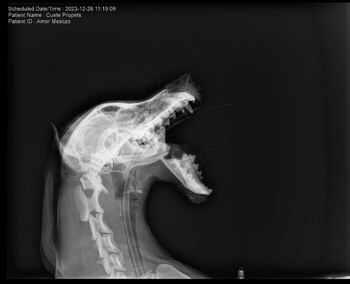

La perrita color café fue rescatada y llevada a la veterinaria ProPets, ubicada en San Benito de Palermo #117, colonia Colinas de San Francisco en León, donde se le estabilizó y recibió atención médica especializada.

“Le realizaron (en la veterinaria) manejo de dolor y la estabilizaron, pues estaba muy mal. El día de hoy se tomaron las placas y análisis de sangre”, indicó a La Silla Rota Clío Sanz, la rescatista.

Sin embargo, para que pueda llevar una mejor calidad de vida es necesario que le implanten una placa de titanio para reparar su mandíbula fracturada.